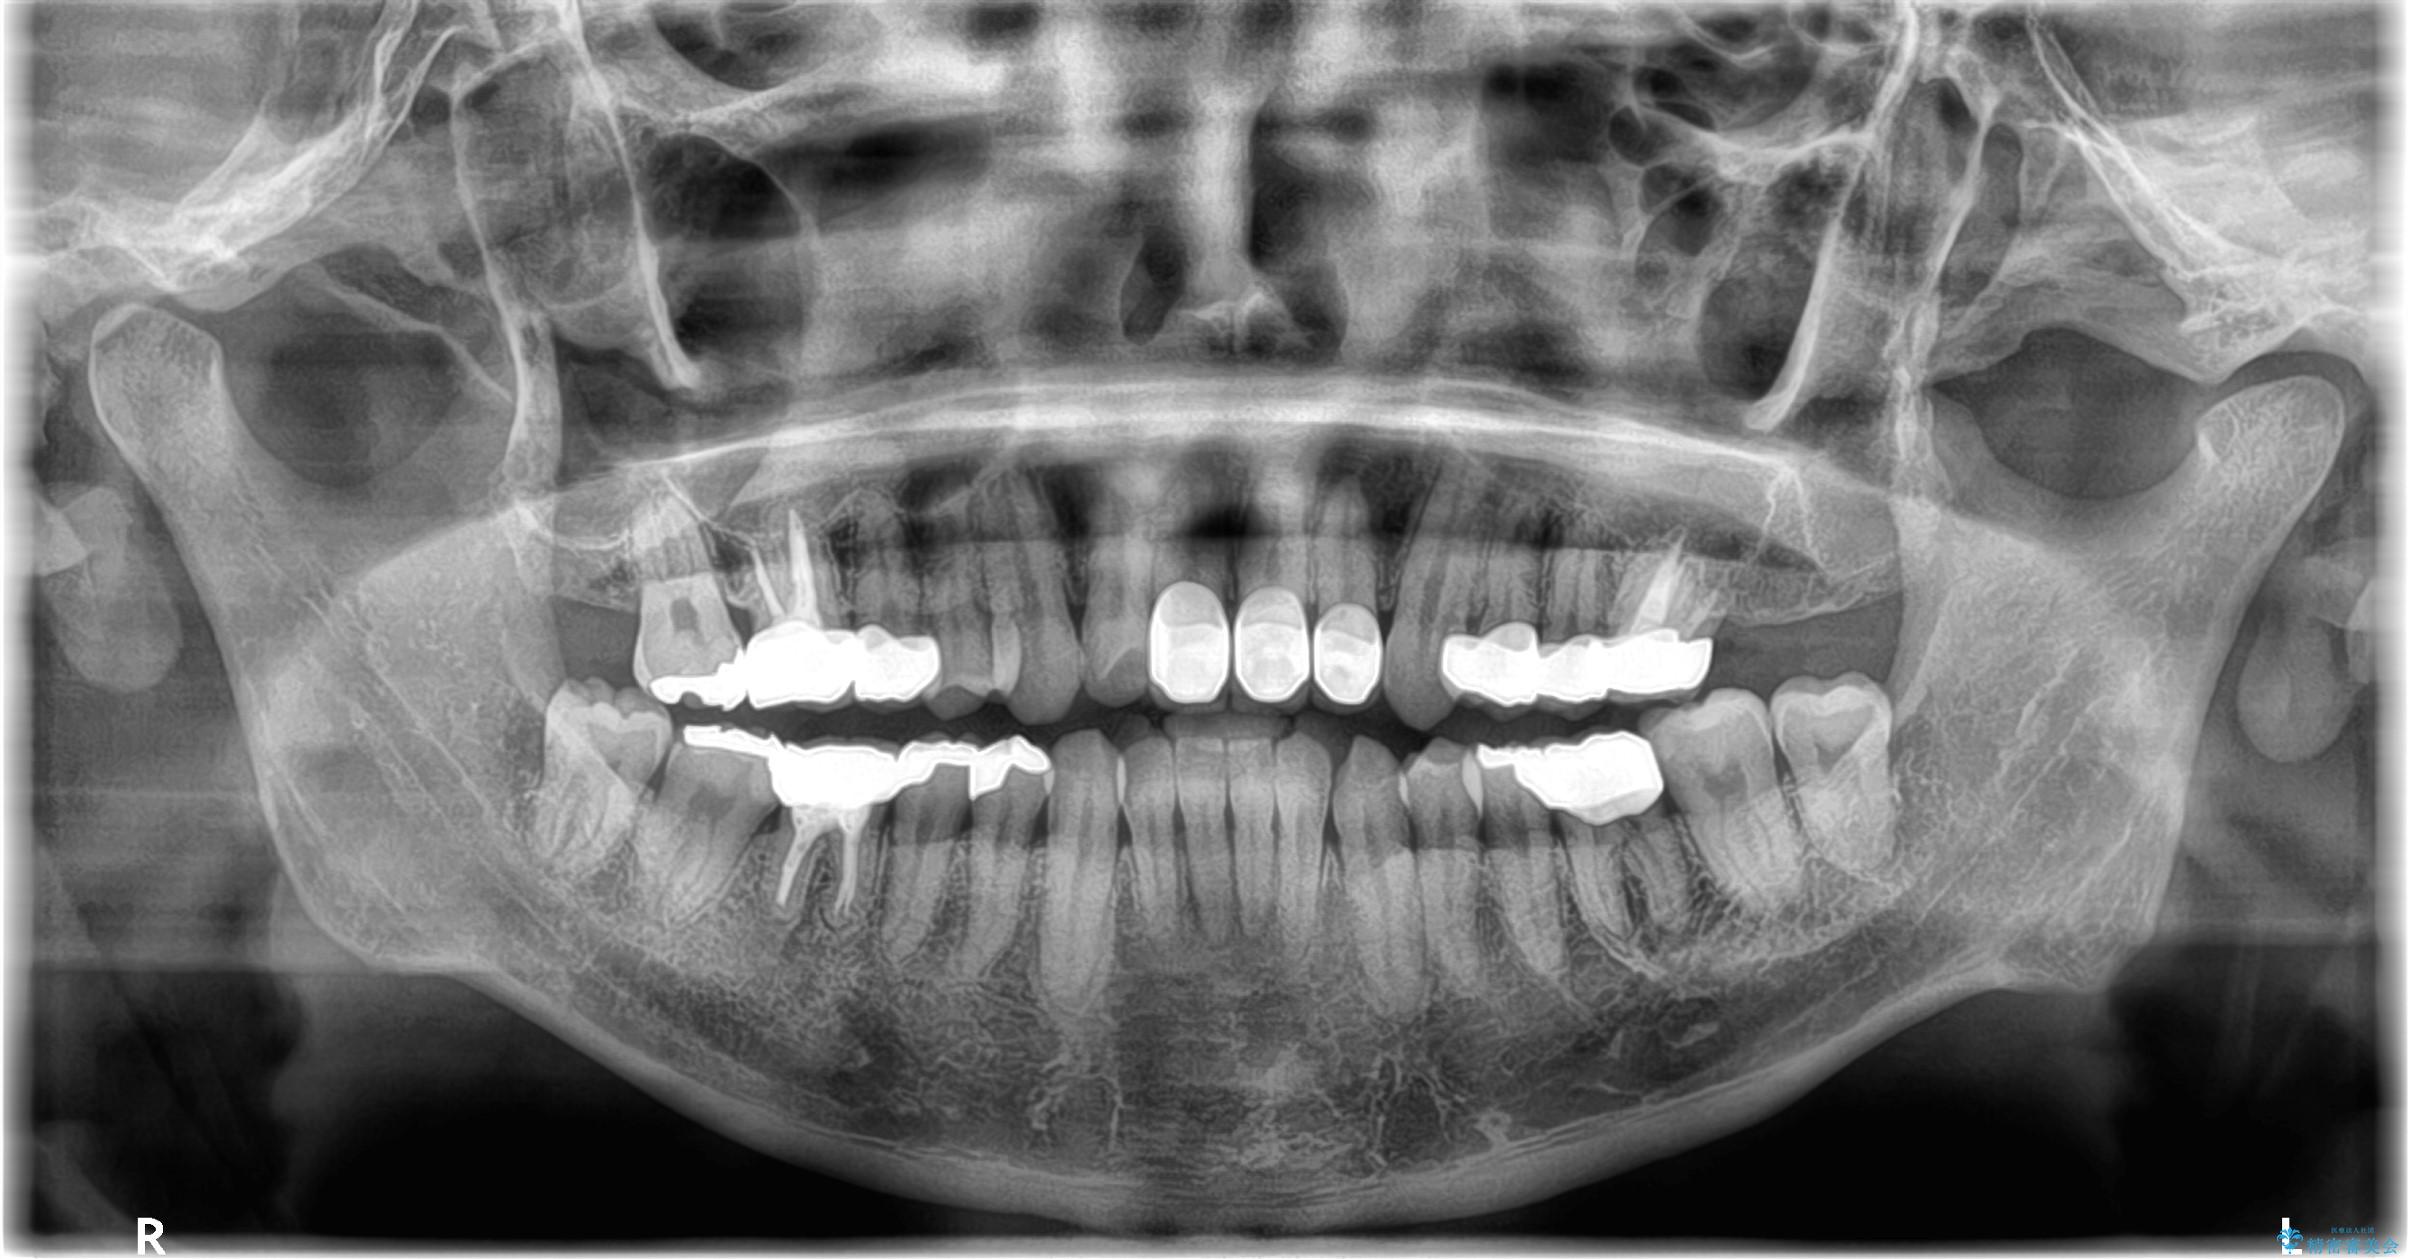

- 突き出た前歯の角度の改善と虫歯治療の改善を求めて来院されました。

虫歯を除去したのち、マウスピース矯正治療を行い、歯並びやがたつきを改善したのち、セラミックに置き換えることで審美性の向上を計画します。